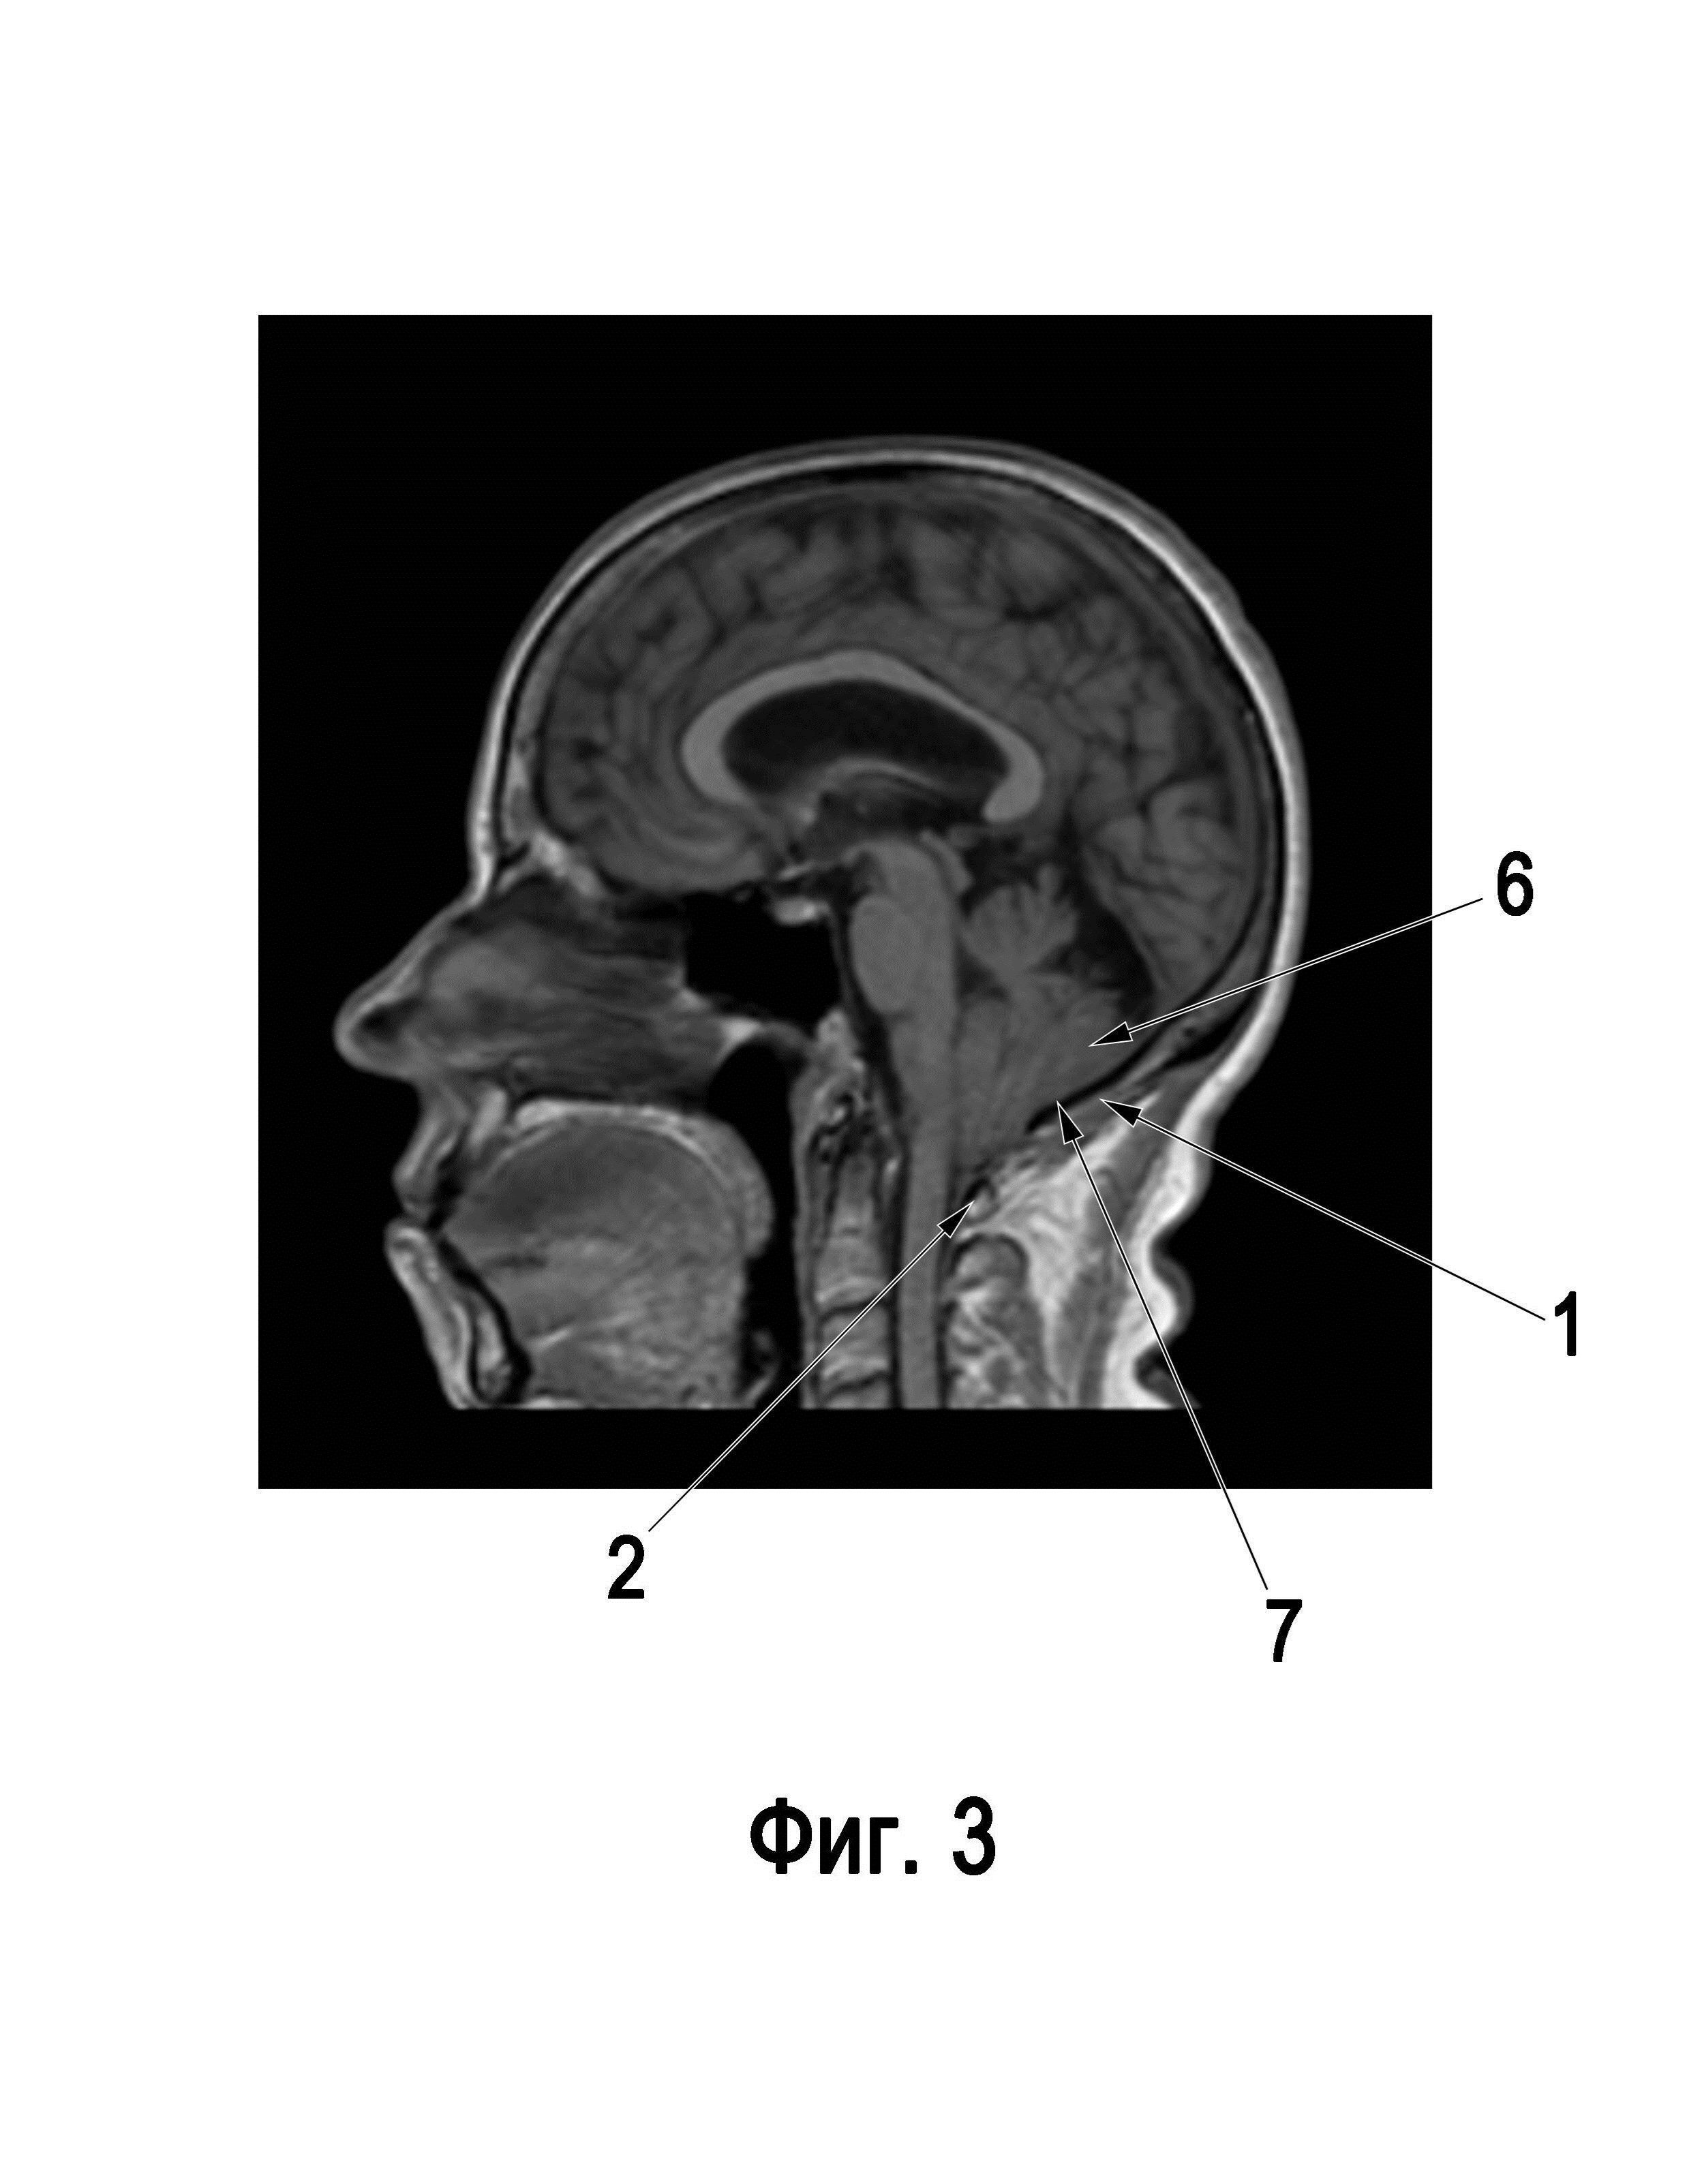

Изобретение относится к области медицины, а именно к нейрохирургии, и может быть использовано для декомпрессии задней черепной ямки при аномалии Киари 1 типа. Известен способ хирургического лечения больных с аномалией Арнольда-Киари [патент RU2635862]. Недостатки этого способа заключаются в том, что декомпрессивную трепанацию выполняют по стандартной методике, что несет в себе значительные риски повреждения твердой мозговой оболочки во время ее выполнения, вероятность вскрытия паутинной оболочки большой затылочной цистерны и, как следствие этих двух событий, худшие клинические исходы хирургического лечения. Известен также способ пластики дуральной воронки при формировании большой затылочной цистерны у больных с мальформацией Киари I-го типа [патент RU2290097]. Недостатки этого способа заключаются в том, что при выполнении резекционной трепанации затылочной кости не учитывается техника выполнения трепанации, что не позволяет минимизировать вероятность хирургических осложнений, связанных с повреждением твердой мозговой оболочки и паутинной оболочки большой затылочной цистерны во время операции. Известен способ пластики костного дефекта после декомпрессивной трепанации задней черепной ямки у пациентов с аномалией Арнольда-Киари I типа [патент RU2578544]. Недостатки этого способа заключаются в необходимости имплантации инородного тела в виде титановой пластины, что повышает риски послеоперационных инфекционных осложнений, а также выполнение резекционной трепанации затылочной кости стандартным методом, что увеличивает вероятность повреждения твердой мозговой оболочки и паутинной оболочки большой затылочной цистерны, что может способствовать развитию осложнений и ухудшению исходов хирургического лечения. Известен способ пластики костного дефекта после декомпрессивной трепанации задней черепной ямки у пациентов с аномалией Арнольда-Киари I типа [патент RU2194459]. Недостатки этого способа заключаются в выполнении резекционной трепанации затылочной кости стандартным методом, что увеличивает вероятность повреждения твердой мозговой оболочки и паутинной оболочки большой затылочной цистерны, что может способствовать развитию осложнений и ухудшению исходов хирургического лечения, а также в сложной пластике твердой мозговой оболочки, что может увеличивать частоту послеоперационных раневых осложнений. Технический результат изобретения заключается в том, что во время операции по декомпрессии задней черепной ямки безопасным способом выполняется резекционная трепанация затылочной кости и дужки первого шейного позвонка, а затем проводится экспансивная пластика твердой мозговой оболочки, что позволяет минимизировать риск повреждения твердой мозговой оболочки и паутинной оболочки большой затылочной цистерны, снизить количество послеоперационных осложнений и улучшить исходы хирургического лечения пациентов с аномалией Киари 1 типа. Сущность изобретения заключается в том, что в способе декомпрессии задней черепной ямки при аномалии Киари 1 типа выполняют кожный разрез в шейно-затылочной области по средней линии, диссекцию мягких тканей по белой линии, далее при помощи бора стачивают наружную часть затылочной кости в области трепанации, после чего выкусывают внутреннюю часть затылочной кости кусачками, резецируют дужку первого шейного позвонка, удаляют атланто-затылочную мембрану, выполняют разрез твердой мозговой оболочки от уровня проекции гемисферы мозжечка до уровня первого шейного позвонка с сохранением паутинной оболочки большой затылочной цистерны, проводят экспансивную пластику твердой мозговой оболочки, послойно наглухо ушивают операционную рану и проводят контроль наличия послеоперационных осложнений. Существует вариант, в котором бор имеет шаровидную, конусовидную, яйцевидную формы, может иметь плоский конец или форму пламени. Существует также вариант, в котором наружной частью затылочной кости, стачиваемой бором, является наружная костная пластинка затылочной кости, а внутренней частью затылочной кости, скусываемой кусачками, является губчатое вещество затылочной кости и внутренняя костная пластинка затылочной кости. Существует также вариант, в котором наружной частью затылочной кости, стачиваемой бором, является наружная костная пластинка и губчатое вещество затылочной кости, а внутренней частью затылочной кости, скусываемой кусачками, является внутренняя костная пластинка затылочной кости. Существует также вариант, в котором резекцию затылочной кости и дужки первого шейного позвонка проводят кусачками Керрисона, Дальгрена, Блюменталя, Бейера или Люэра. Существует также вариант, в котором разрез твердой мозговой оболочки может быть S-образным, Y-образным, линейным или диагональным. Существует также вариант, в котором экспансивную пластику твердой мозговой оболочки проводят с использованием аутотрансплантата широкой фасции бедра. Существует также вариант, в котором экспансивную пластику твердой мозговой оболочки проводят с использованием синтетического протеза оболочки. Существует также вариант, в котором для контроля наличия послеоперационных осложнений выполняют компьютерную томографию головного мозга высокого разрешения в режиме мультиспиральной компьютерной томографии с толщиной среза от 0,5 мм до 1 мм. Существует также вариант, в котором для контроля наличия послеоперационных осложнений выполняют магнитно-резонансную томографию головного мозга в режимах T1, Т2, FLAIR без контрастного усиления. На фиг.1 изображена схема выполнения резекционной трепанации затылочной кости. На фиг.2 изображена схема выполнения разрезов твердой мозговой оболочки. На фиг.3 изображена магнитно-резонансная томография у пациента с аномалией Киари 1 типа. На фиг.4 изображена компьютерная томография пациента с аномалией Киари 1 типа после проведения декомпрессии задней черепной ямки и экспансивной пластики твердой мозговой оболочки. Способ декомпрессии задней черепной ямки при аномалии Киари 1 типа реализуют следующим образом. Выполняют кожный разрез, резекционную трепанацию затылочной кости 1, ламинэктомию дужки первого шейного позвонка 2 и экспансивную пластику твердой мозговой оболочки 3. Отличительные признаки изобретения заключаются в том, что сначала выполняют кожный разрез в шейно-затылочной области по средней линии, диссекцию мягких тканей по белой линии, далее при помощи бора 4 стачивают наружную часть затылочной кости 1 в области трепанации, после чего выкусывают внутреннюю часть затылочной кости 1 кусачками 5, резецируют дужку первого шейного позвонка 2, удаляют атланто-затылочную мембрану, выполняют разрез твердой мозговой оболочки 3 от уровня проекции гемисферы мозжечка 6 до уровня первого шейного позвонка 2 с сохранением паутинной оболочки большой затылочной цистерны 7, проводят экспансивную пластику твердой мозговой оболочки 3, послойно наглухо ушивают операционную рану и проводят контроль наличия послеоперационных осложнений. Существует вариант, в котором бор 4 имеет шаровидную, конусовидную, яйцевидную формы, может иметь плоский конец или форму пламени. Такой вариант позволяет максимально безопасно провести резекционной трепанацию затылочной кости, минимизировать риски хирургического лечения и сохранить ликвородинамику краниовертебрального перехода, необходимую для регрессии клинических симптомов и улучшения исходов хирургического лечения пациентов с аномалией Киари 1 типа. Существует также вариант, в котором наружной частью затылочной кости 1, стачиваемой бором 4, является наружная костная пластинка 8 затылочной кости 1, а внутренней частью затылочной кости, скусываемой кусачками, является губчатое вещество 9 затылочной кости 1 и внутренняя костная пластинка 10 затылочной кости 1. Такой вариант позволяет применять данный метод с учетом различной анатомии затылочной кости у пациентов с аномалией Киари 1 типа и безопасно выполнять резекционную трепанацию затылочной кости, что улучшает исходы хирургического лечения данных пациентов. Существует также вариант, в котором наружной частью затылочной кости 1, стачиваемой бором 4, является наружная костная пластинка 8 и губчатое вещество 9 затылочной кости 1, а внутренней частью затылочной кости 1, скусываемой кусачками, является внутренняя костная пластинка 10 затылочной кости 1. Такой вариант позволяет уменьшить количество послеоперационных осложнений и улучшить исходы хирургического лечения у пациентов с аномалией Киари 1 типа. Существует также вариант, в котором резекцию затылочной кости 1 и дужки первого шейного позвонка 2 проводят кусачками 5 Керрисона, Дальгрена, Блюменталя, Бейера или Люэра. Такой вариант позволяет выполнять второй этап в резекционной трепанации затылочной кости различными видами костных кусачек, что дает возможность выполнять его безопасно, что улучшает исходы хирургического лечения, а также делает этот способ более доступным различным хирургическим клиникам. Существует также вариант, в котором разрез твердой мозговой оболочки может быть S-образным, Y-образным, линейным или диагональным. Такой вариант позволяет применять данный метод с различными вариантами разреза твердой мозговой оболочки, что делает данный метод более доступным, позволяет применять у более широкого круга пациентов с аномалией Киари 1 типа и приводит к улучшению результатов хирургического лечения. Существует вариант, в котором экспансивную пластику твердой мозговой оболочки 3 проводят с использованием аутотрансплантата широкой фасции бедра. Такой вариант позволяет выполнить надежную экспансивную пластику твердой мозговой оболочки и улучшить результаты хирургического лечения. Существует также вариант, в котором экспансивную пластику твердой мозговой оболочки 3 проводят с использованием синтетического протеза оболочки. Такой вариант позволяет провести экспансивную пластику твердой мозговой оболочки при невозможности проведения с использованием аутотрансплантата широкой фасции бедра, сделать этот способ более доступным и улучшить результаты хирургического лечения. Существует также вариант, в котором для контроля наличия послеоперационных осложнений выполняют компьютерную томографию головного мозга высокого разрешения в режиме мультиспиральной компьютерной томографии с толщиной среза от 0,5 мм до 1 мм. Такой вариант позволяет снизить количество возможных послеоперационных осложнений. Существует вариант, в котором для контроля наличия послеоперационных осложнений выполняют магнитно-резонансную томографию головного мозга в режимах T1, Т2, FLAIR без контрастного усиления. Такой вариант позволяет снизить количество возможных послеоперационных осложнений. На фиг.1 изображена схема выполнения резекционной трепанации затылочной кости 1, где изображено, как при помощи бора 4 стачивают наружную часть затылочной кости 1 в области трепанации, которой является является наружная костная пластинка 8 и губчатое вещество 9 затылочной кости 1, после чего выкусывают внутреннюю часть затылочной кости 1 кусачками 5, которой является внутренняя костная пластинка 10 затылочной кости 1. На фиг.2 изображена схема выполнения разрезов твердой мозговой оболочки 3 после резекционной трепанации затылочной кости 1 и резекции дужки первого шейного позвонка 2, где показано, что разрез твердой мозговой оболочки 3 может быть S-образным (рис. А), Y-образным (рис. Б), линейным (рис. В) или диагональным (рис. Г). На фиг.3 изображена магнитно-резонансная томография у пациента с аномалией Киари 1 типа, где визуализируются затылочная кость 1, душка первого шейного позвонка, гемисфера мозжечка 6 и большая затылочная цистерна 7. На фиг.4 изображена компьютерная томография пациента с аномалией Киари 1 типа после проведения декомпрессии задней черепной ямки и экспансивной пластики твердой мозговой оболочки 3, показывающая отсутствие послеоперационных хирургических осложнений. Клинический пример Пациентка, 64 лет, поступила в клинику с жалобами на боль по задней поверхности шеи и в затылочной области в течение последних 20 лет. Предпринимались попытки консервативного лечения без значимого клинического эффекта. Пациентка неоднократно выполняла МРТ головного мозга, где в 2010 году была выявлена аномалия Киари 1 типа. За отсутствием другой клинической симптоматики, кроме цервикалгии, хирургическое лечение пациентке предложено не было, было рекомендовано наблюдение. Около 2 лет назад отметила появление затруднения при глотании (особенно твердой пищи), которое со временем прогрессировало. По данным последнего МРТ исследования - опущение миндаликов мозжечка ниже линии Мак-Рея, признаки аномалии Киари 1 типа (фиг.3). Госпитализирована в клинику для проведения хирургического лечения. 12.08.2020 была проведена операция по декомпрессии задней черепной ямки. В процессе операции в положении пациентки лежа на животе произведен линейный разрез кожи и мягких тканей в шейно-затылочной области по средней линии. После препаровки мягких тканей и выделения апоневротического лоскута при помощи бора осуществлена резекция наружной костной пластинки и губчатого вещества чешуи затылочной кости в области заднего полукольца большого затылочного отверстия и дужки первого шейного позвонка. Твердая мозговая оболочка вскрыта линейным разрезом над каудальными отделами задней черепной ямки и верхними шейными сегментами спинного мозга, целостность паутинной оболочки большой затылочной цистерны не нарушена. Выполнена экспансивная пластика твердой мозговой оболочки надкостничным аутотрансплантатом. Операционная рана многократно промыта физиологическим раствором. Послойные швы на мягкие ткани. Послеоперационный период протекал гладко, без осложнений. В неврологическом статусе отрицательной динамики не отмечено. На послеоперационной компьютерной томографии (фиг.4) определяются послеоперационные изменения, желудочковая система не расширена, не смещена. Осложнений не выявлено. Послеоперационная рана заживает первичным натяжением, воспалительные изменения не выражены, швы состоятельны. На 5 сутки после операции в удовлетворительном состоянии пациентка выписана под наблюдение врачей по месту жительства. Катамнез пациентки 2,5 года, отмечает уменьшение выраженности клинической симптоматики в виде регресса нарушений глотания и уменьшение головной боли. Данный клинический пример демонстрирует безопасность применения предлагаемого способа декомпрессии задней черепной ямки при аномалии Киари 1 типа, возможность уменьшения послеоперационных хирургических осложнений путем его использования и улучшение исходов хирургического лечения пациентов с аномалией Киари 1 типа. То, что в способе декомпрессии задней черепной ямки при аномалии Киари 1 типа, включающем выполнение кожного разреза, резекционную трепанацию затылочной кости 1, ламинэктомию дужки первого шейного позвонка 2 и экспансивную пластику твердой мозговой оболочки 3, отличающийся тем, что сначала выполняют кожный разрез в шейно-затылочной области по средней линии, диссекцию мягких тканей по белой линии, далее при помощи бора 4 стачивают наружную часть затылочной кости 1 в области трепанации, после чего выкусывают внутреннюю часть затылочной кости 1 кусачками 5, резецируют дужку первого шейного позвонка 2, удаляют атланто-затылочную мембрану, выполняют разрез твердой мозговой оболочки 3 от уровня проекции гемисферы мозжечка 6 до уровня первого шейного позвонка 2 с сохранением паутинной оболочки большой затылочной цистерны 7, проводят экспансивную пластику твердой мозговой оболочки 3, послойно наглухо ушивают операционную рану и проводят контроль наличия послеоперационных осложнений, приводит к безопасному выполнению резекционной трепанации, позволяет уменьшить выраженность клинической симптоматики у пациентов, уменьшить риски хирургических осложнений и улучшить исходы хирургического лечения. То, что бор 4 имеет шаровидную, конусовидную, яйцевидную формы, может иметь плоский конец или форму пламени, позволяет максимально безопасно провести резекционной трепанацию затылочной кости, минимизировать риски хирургического лечения и сохранить ликвородинамику краниовертебрального перехода, необходимую для регрессии клинических симптомов и улучшения исходов хирургического лечения пациентов с аномалией Киари 1 типа То, что наружной частью затылочной кости 1, стачиваемой бором 4, является наружная костная пластинка 8 затылочной кости 1, а внутренней частью затылочной кости, скусываемой кусачками, является губчатое вещество 9 затылочной кости 1 и внутренняя костная пластинка 10 затылочной кости 1, позволяет применять данный метод с учетом различной анатомии затылочной кости у пациентов с аномалией Киари 1 типа и безопасно выполнять резекционную трепанацию затылочной кости, что улучшает исходы хирургического лечения данных пациентов. То, что наружной частью затылочной кости 1, стачиваемой бором 4, является наружная костная пластинка 8 и губчатое вещество 9 затылочной кости 1, а внутренней частью затылочной кости 1, скусываемой кусачками, является внутренняя костная пластинка 10 затылочной кости 1, позволяет уменьшить количество послеоперационных осложнений и улучшить исходы хирургического лечения у пациентов с аномалией Киари 1 типа. То, что резекцию затылочной кости 1 и дужки первого шейного позвонка 2 проводят кусачками 5 Керрисона, Дальгрена, Блюменталя, Бейера или Люэра, позволяет выполнять второй этап в резекционной трепанации затылочной кости различными видами костных кусачек, что дает возможность выполнять его безопасно, что улучшает исходы хирургического лечения, а также делает этот способ более доступным различным хирургическим клиникам. То, что разрез твердой мозговой оболочки может быть S-образным, Y-образным, линейным или диагональным, позволяет применять данный метод с различными вариантами разреза твердой мозговой оболочки, что делает данный метод более доступным, позволяет применять у более широкого круга пациентов с аномалией Киари 1 типа и приводит к улучшению результатов хирургического лечения. То, что экспансивную пластику твердой мозговой оболочки 3 проводят с использованием аутотрансплантата широкой фасции бедра, позволяет выполнить надежную экспансивную пластику твердой мозговой оболочки и улучшить результаты хирургического лечения. То, что экспансивную пластику твердой мозговой оболочки 3 проводят с использованием синтетического протеза оболочки, позволяет провести экспансивную пластику твердой мозговой оболочки при невозможности проведения с использованием аутотрансплантата широкой фасции бедра, сделать этот способ более доступным и улучшить результаты хирургического лечения. То, что для контроля наличия послеоперационных осложнений выполняют компьютерную томографию головного мозга высокого разрешения в режиме мультиспиральной компьютерной томографии с толщиной среза от 0,5 мм до 1 мм, позволяет снизить количество возможных послеоперационных осложнений. То, что для контроля наличия послеоперационных осложнений выполняют магнитно-резонансную томографию головного мозга в режимах T1, Т2, FLAIR без контрастного усиления, позволяет снизить количество возможных послеоперационных осложнений.